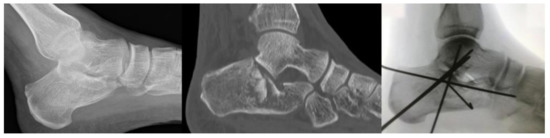

2.1. Surgical Procedure